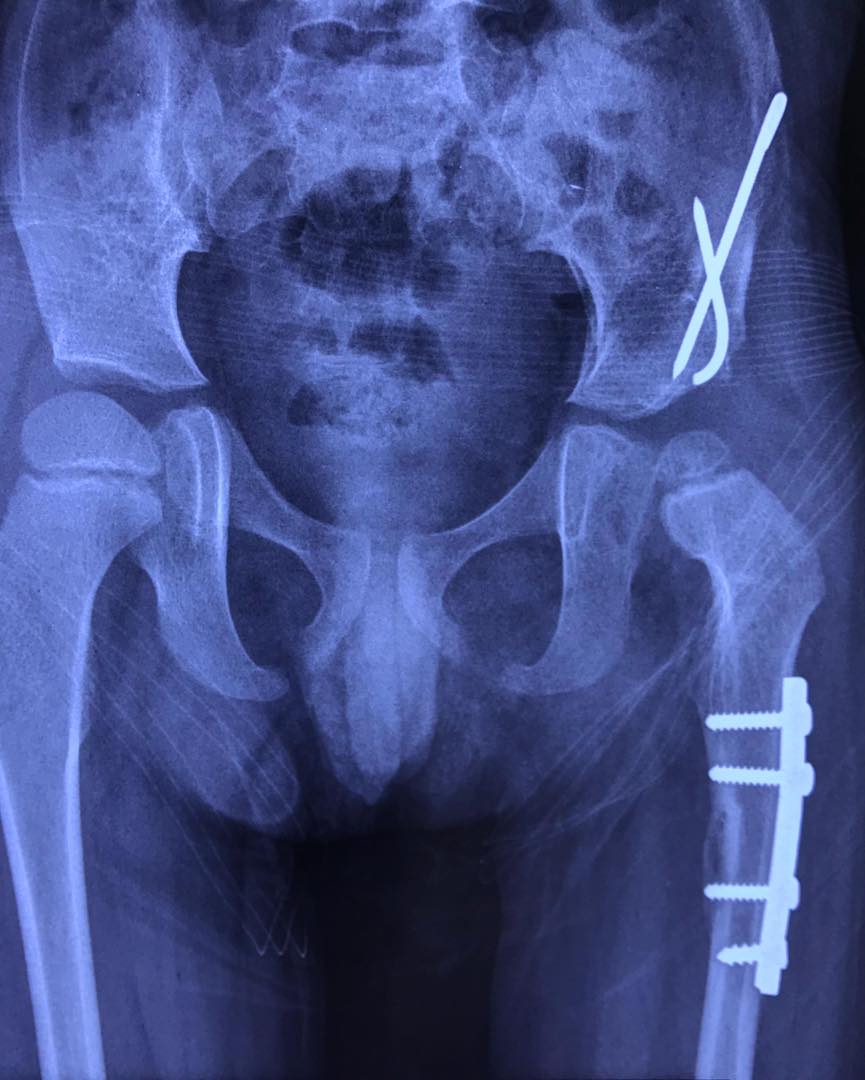

Atrogriposis con cadera luxada

Este superhéroe se llama Jesús Fernando y actualmente tiene cinco años. Nació con artrogriposis y con la cadera izquierda luxada. Recibió tratamiento en un hospital público, pero sin éxito; incluso la cirugía realizada fue fallida. Les comparto las fotografías de cómo llegó a mi consulta hace un año, y las imágenes después del tratamiento con yesos e intervenciones quirúrgicas: dos en los pies y una en la cadera. Mi valiente pacientito llegó sin poder caminar, ¡y ahora ya anda jugando por todos lados! Felicidades a sus papás por el esfuerzo para darle a Jesús Fernando este enorme regalo. Me siento muy agradecido por su confianza.